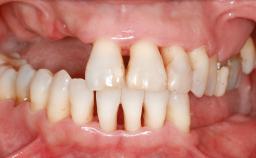

Ridge Preservation and Implant Placement for a Fixed Dental Prosthesis After a Car Accident

It is well known to clinicians that any removal of teeth will, over time, cause the dimensions of the alveolar ridge to be reduced by resorption of the bundle bone and by changes related to external modeling. This development is particularly evident in the crestal region with its thin buccal bone that consists of bundle bone almost entirely. The facial bone will rapidly resorb as blood supply from the periodontal ligament gets disrupted (Araújo and Lindhe 2005). There is no reason why traumatic tooth loss should not have the same consequences. It takes more than achieving implant osseointegration for a treatment outcome to be considered successful. No deficiency of bone or soft tissue is acceptable when an ideal esthetic outcome is the goal. Several articles (Sanz and coworkers 2011; Vignoletti and coworkers 2011) have reported on techniques of improving the alveolar ridge for implant treatment, notably focusing on protecting tissues from resorption.

Bone Volume Horizontally and vertically sufficient Horizontally deficient Deficient vertically or deficient vertically AND horizontally

Bone Volume Deficient vertically or deficient vertically AND horizontally